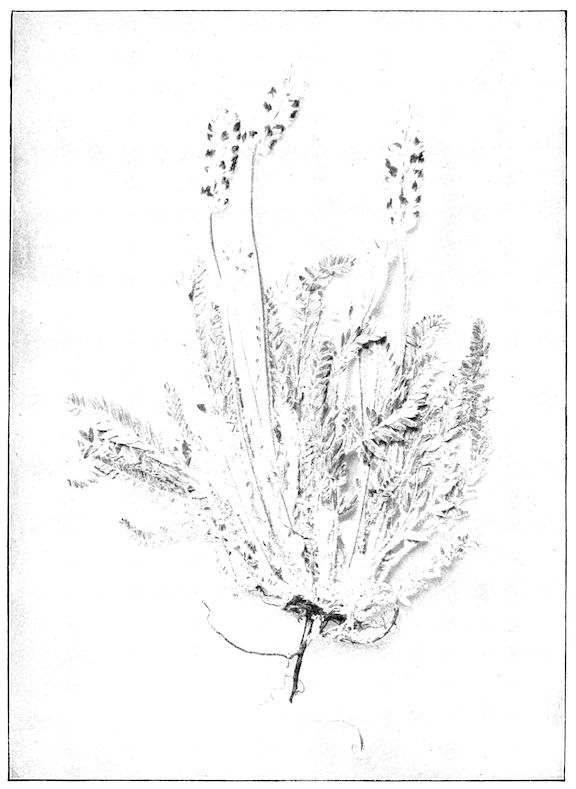

Fig. 8.—Transverse section through the middle region of the face in a pig suffering from osseous cachexia.

18In the final stages, the bones may be cut with a knife, and a time arrives when bony tissue seems completely to have disappeared; thus, as shown in Fig. 8 herewith, it was possible to cut the entire head of a pig into thin slices without the slightest difficulty. All parts of the head had been affected by the softening change.